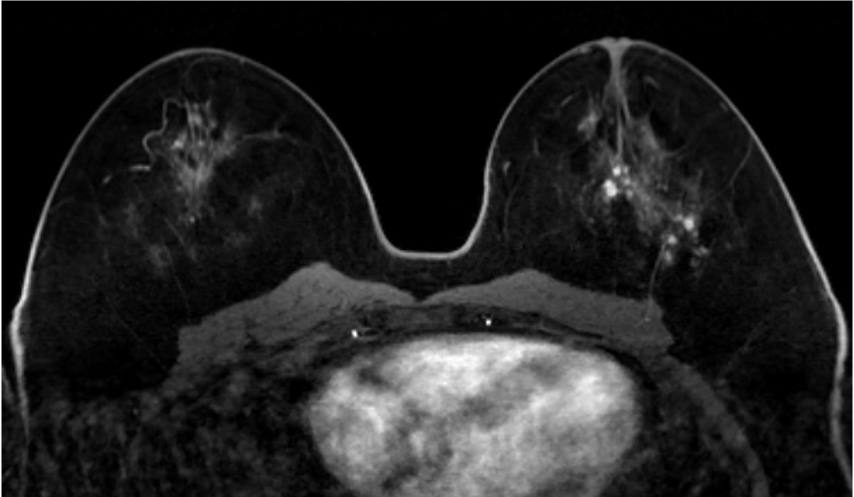

4. ダイナミックMRI (造影前 早期相 遅延相)

乳腺散在性の乳房であるが、造影早期から背景乳腺の大部分が造影されており、BPEはmarkedである。DCISの病変(矢印)は、clumped、segmental distributionの腫瘤非形成性病変(Non-mass enhancement)を示しているが、BPEが強く、広がり診断が困難である。